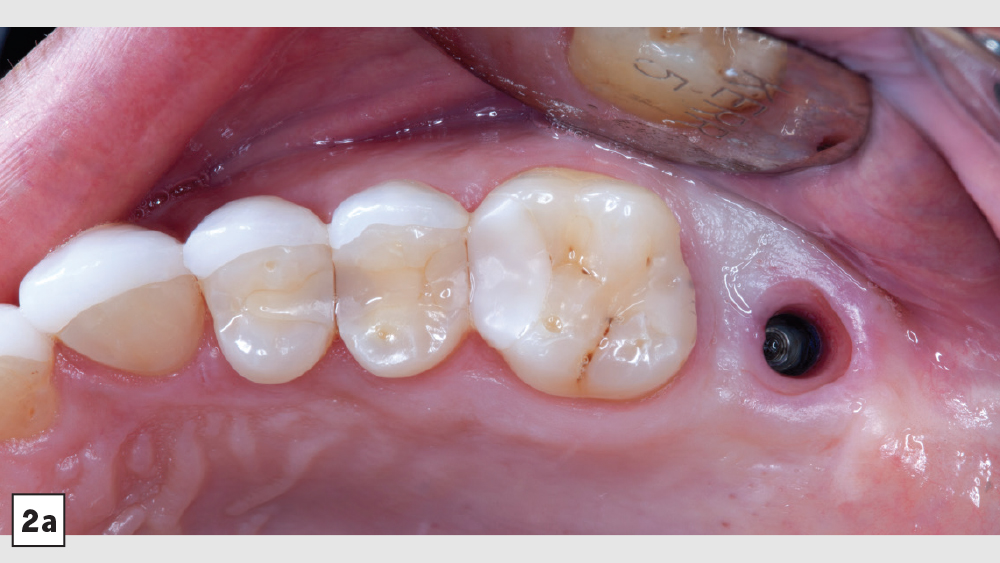

A patient presented with issues concerning a screw-retained crown in the area of tooth #15. She complained that the crown felt loose, was causing food entrapment and was difficult to clean. Upon examination, it appeared that the prosthetic screw was loose and the restoration was mobile. Removal of the crown confirmed that the current design of the prosthesis created a food trap and was not conducive to soft-tissue health. We agreed that the restoration needed to be replaced. A screwmentable restoration was the optimal solution because the malposition of the implant could be corrected by a custom abutment, thereby minimizing the cantilever. We wanted to improve the direction of loading and lessen sheer forces on the implant site by building the restoration out with the titanium structure of the custom abutment. At the same time, because the implant site was in a hard-to-reach area from which cement removal would have been difficult, screw retention was preferred.